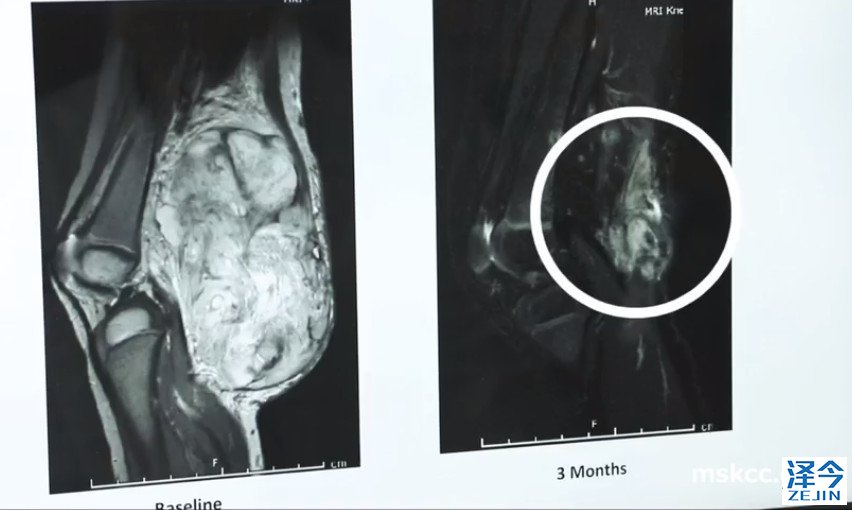

虽然她在服药几个月后,影像学检查发现复发很少,她持续服用药物。如今,安娜的扫描显示:没有活性的证据,也就是说癌症病灶没有活性,不会再有复发转移的机会,癌症没有了!

“我们在安娜身上取得了令人惊叹的成就,”Drilon博士说。“Larotrectinib让她再次以有意义的方式过上了自己想要的生活。如果她的癌症没有经过TRK融合检测,结局将大相径庭!”